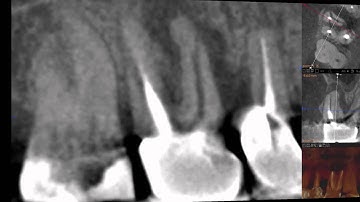

Endo Analysis Root Fracture | Ez3D-i | Vatech